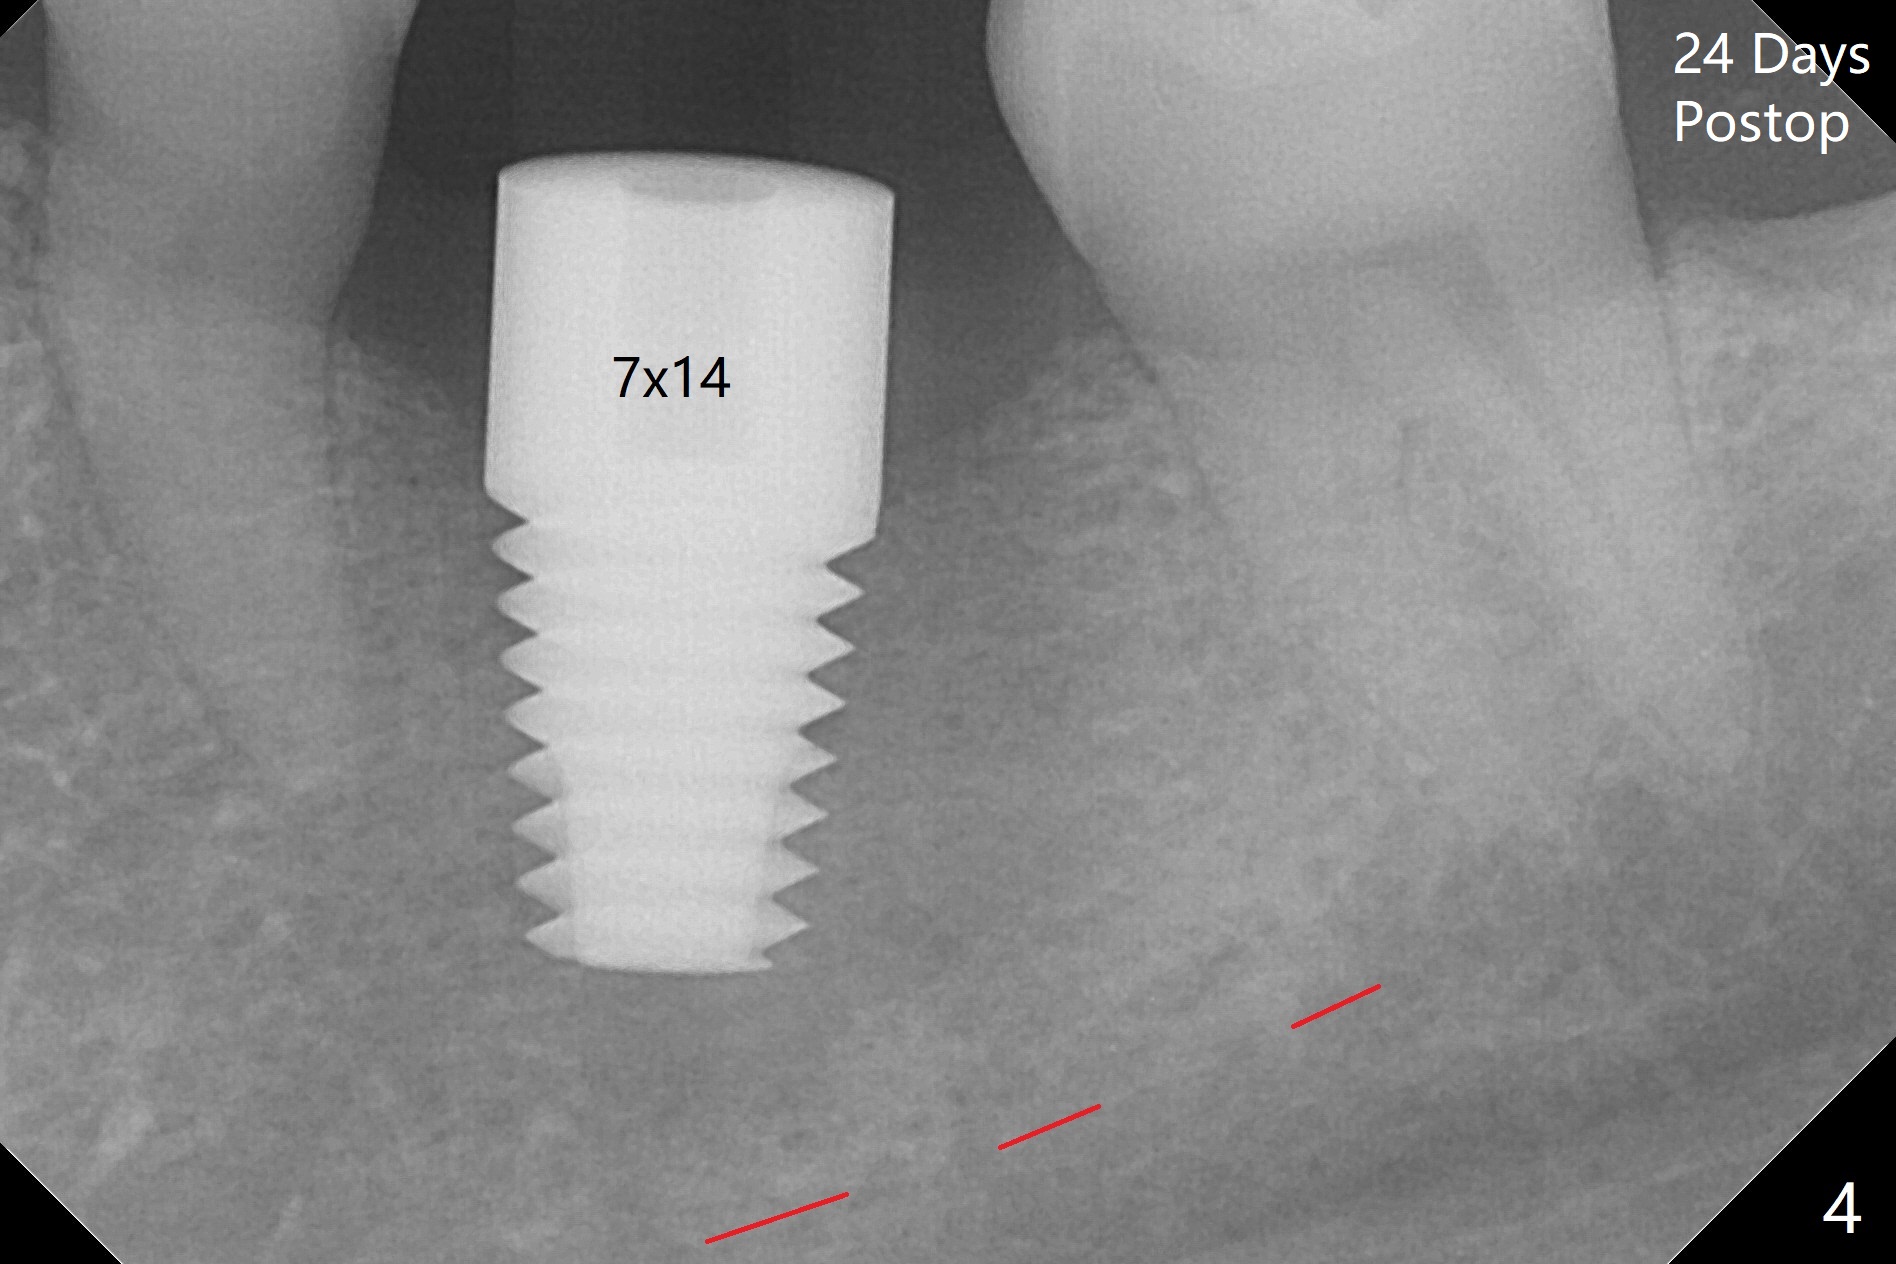

After 4.0x10 mm drill with 9 mm offset for 4.5x10 mm bone-level implant at #19, a 4.5x17 mm tissue level tap is inserted with apparently low torque (probably without reaching the depth). When a 4.5x14 mm tissue level implant is placed with high torque, a 4.5x7.3 mm drill is used for ~ 6.5 mm. The implant loses the primary stability with over-insertion (Fig.1). When an abutment is placed, the implant is critically loose. Mixture of autogenous bone, Osteogen and allograft is placed in the osteotomy. The implant regains stability with better placement level for restoration (Fig.2). In fact the bone density around the implant increases (Fig.2 *). For the first 7 days postop, the patient has to take Advil. When he returns for follow up 8 days postop (Fig.3), the pain decreases, while there is minor degree of lower lip paresthesia. Medrol Dose Pak and Tylenol III are prescribed. The implant is loose 24 days postop; after removal of the implant and apparently infected bone graft, a 7x14 mm dummy implant is inserted with <20 Ncm and 3-4 mm clearance (Fig.4). A longer dummy implant seems to improve stability (Fig.5). So does the definitive implant (Fig.6,7, 25 Ncm), but it is placed low. The gingiva looks healthy 13 days postop (2nd placement). A healing cap will be placed for restoration ~ 3 months postop. CT will be taken if the implant needs to be backed up to determine whether there is enough bone buccolingually. Due to coronavirus and prolonged placement of a healing abutment with poor oral hygiene, the buccal gingiva of the implant is erythematous 1 year postop (Fig.8 healing cap just removed) with bone loss (Fig.9,10 *). Sticky bone seems to be necessary. A 6x5 mm abutment with slots will be placed to hold periodontal dressing in place.